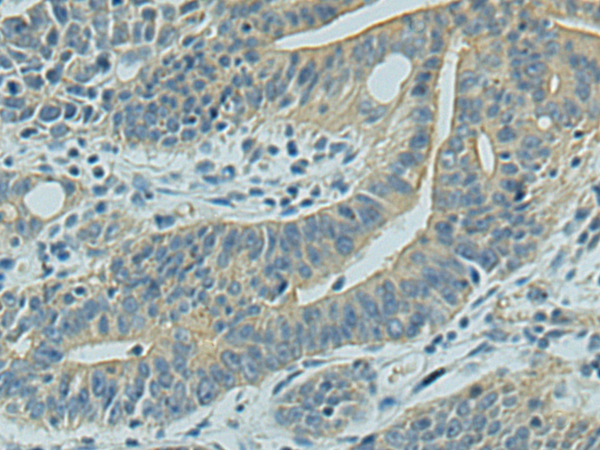

IHC positive control: |

Human gastric cancer and Human tonsil |